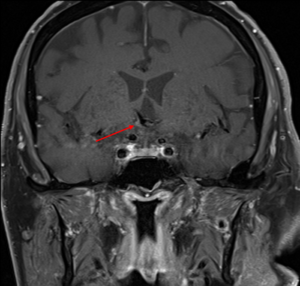

The patient also complained of headaches in the morning, but his IOP remained within normal range. He reported significantly clearer vision in the morning after awakening and that his vision worsened throughout the day. The patient was referred for an MRI of the brain and orbits with and without gadolinium contrast dye concentrating on the right parietal lobe and the orbits. The images showed tortuous and enlarged anterior and middle cerebral arteries that distended and bilaterally exerted a mass effect upon the optic chiasm and optic tracts (Figure 2). The anterior and middle cerebral arteries appeared to be dolichoectatic and resting on the floor of the third ventricle (Figure 3). This confirmed the diagnosis of dolichoectasia.

![]() Figure 3. MRI of the dolichoectatic middle cerebral arteries visible under the floor of the third ventricle. Click to enlarge |